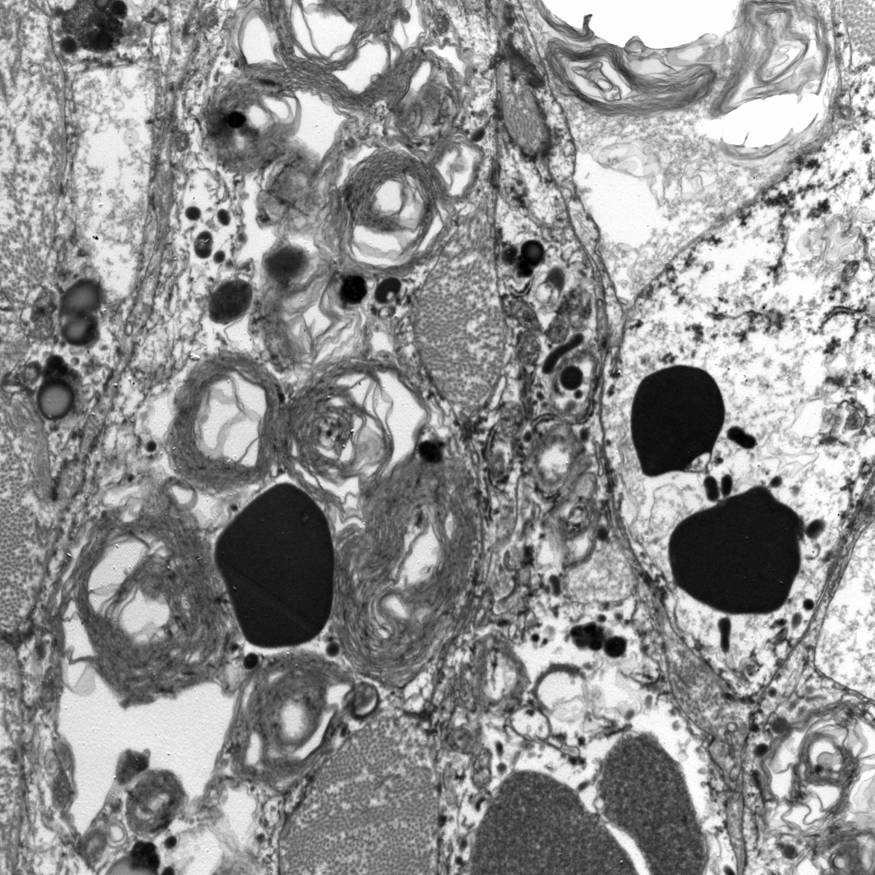

Electron microscopy description

- Abundant intracytoplasmic lipid droplets of varying sizes

- Prominent microvillous projections along cell borders

- Abundant smooth endoplasmic reticulum

- Prominent, round to oval mitochondria; cristae may have tubular to vesicular (zona fasciculata) or lamellar (zona reticularis) profile